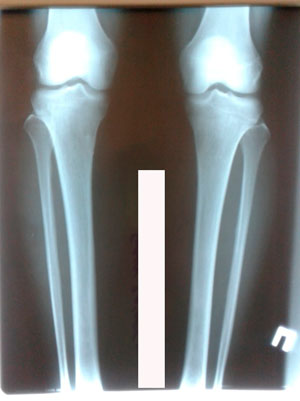

Исходник - 32 года.

Дата операции - 19.03.2020

image-19-03-20-12-29-2.jpg

image-19-03-20-12-29-1.jpg

image-18-03-20-04-34.jpg